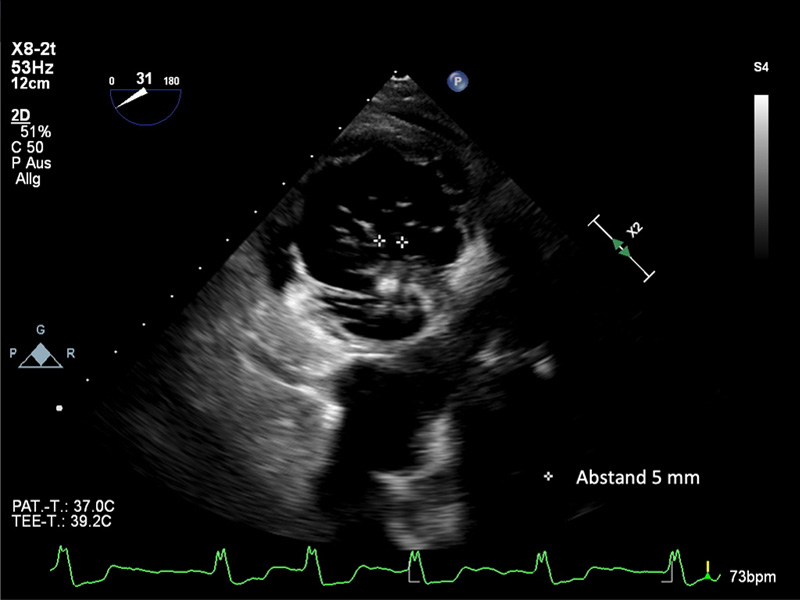

Eine weitere Verringerung des zentralen Koaptationsdefektes auf 5mm ist zu erkennen.

Alternative Verwendung des transgastrischen Blicks für den Greifvorgang, da die Sicht in den typischen Achsen durch die zuvor implantierten TriClips eingeschränkt ist. Es ist zu erkennen, wie die Spitzen der Segel während des Schließvorgangs in den TriClip XTW laufen.